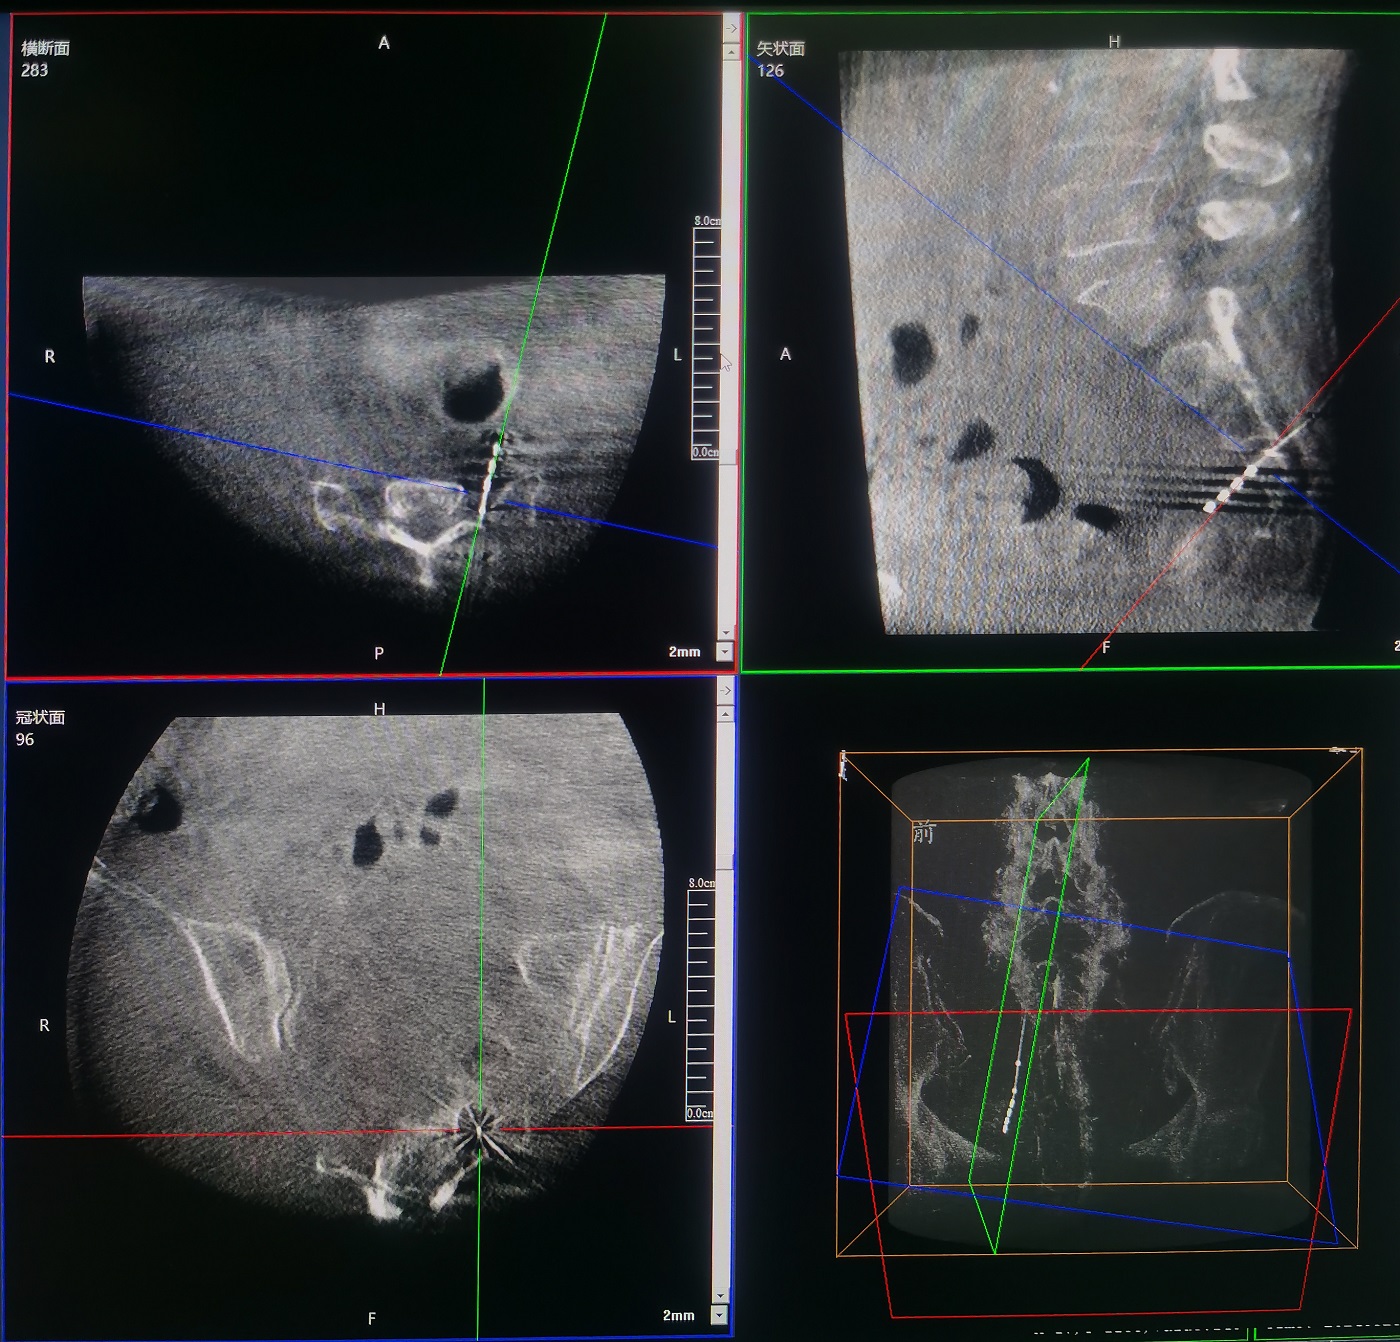

術(shù)中,運(yùn)用普愛醫(yī)療三維C形臂環(huán)掃,采集骶骨區(qū)域三維圖像,在機(jī)器人導(dǎo)航界面上進(jìn)行路徑規(guī)劃,自動(dòng)引導(dǎo)進(jìn)入骶3神經(jīng)孔。

原本需要反復(fù)透視比較和定位的骶3神經(jīng)孔,通過機(jī)器人的智能算法,一次性即可準(zhǔn)確定位,靶向進(jìn)入。

整個(gè)手術(shù)過程清晰流暢,穿刺傷口小。經(jīng)過三維C形臂透視確認(rèn),刺激器位置精準(zhǔn),與術(shù)前規(guī)劃位置一致。